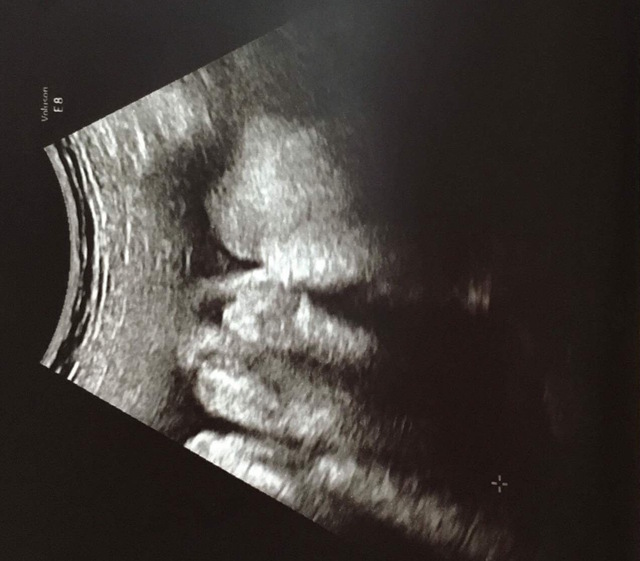

36週1日(36w1d・女の子)|aya.i さん(27歳)

エコー写真撮影時のエピソード:

29週の頃、羊水過少で緊急入院になりました。約半月入院したけど、原因は分からず、、、里帰り出産を希望しており、34週の時、実家に帰りました。初めての里帰り先での病院受診で、帝王切開になる事が決まり、その次の週に今回のエコー写真が撮られました。まだ出てきたくないのか、両手で顔を隠していました。予定日より3週間早く、37週の時に無事生まれてきてくれて、エコー写真と同じように顔に手を置いていました。